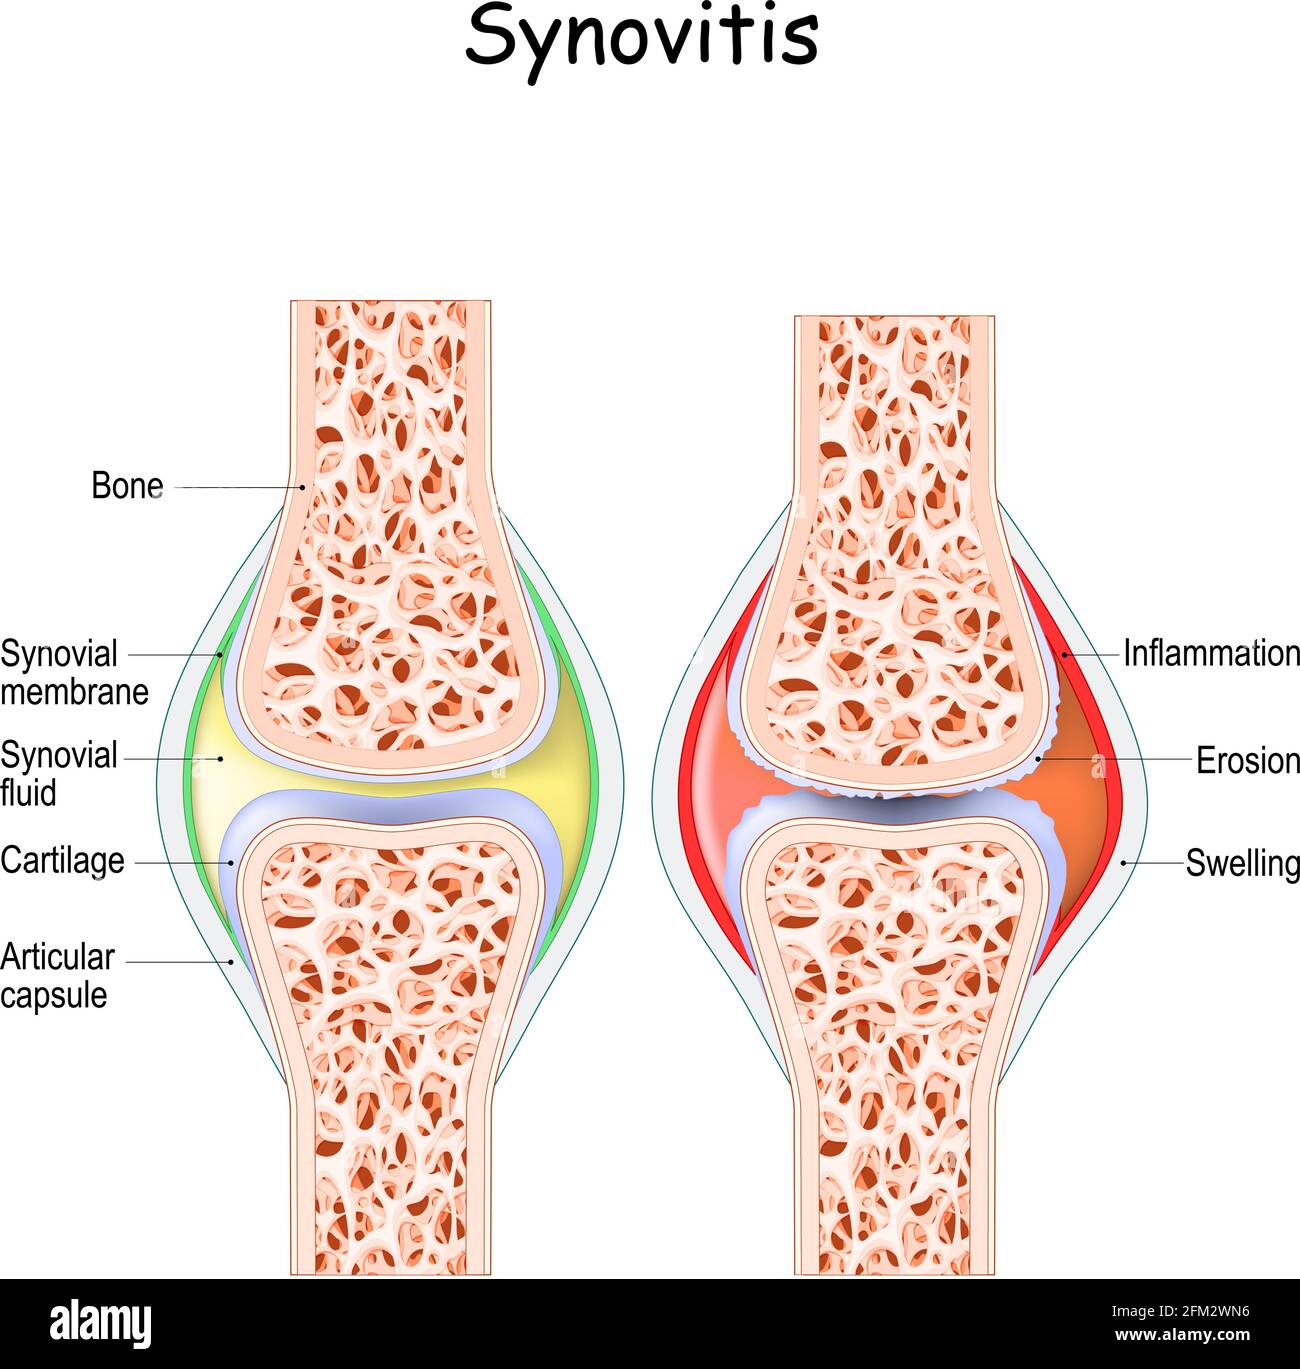

synovitis. Close-up. comparison and difference between a healthy joint and a joint with inflammation of the synovial membrane. Signs and symptoms Stock Vectorhttps://www.alamy.com/image-license-details/?v=1https://www.alamy.com/synovitis-close-up-comparison-and-difference-between-a-healthy-joint-and-a-joint-with-inflammation-of-the-synovial-membrane-signs-and-symptoms-image425406050.html

synovitis. Close-up. comparison and difference between a healthy joint and a joint with inflammation of the synovial membrane. Signs and symptoms Stock Vectorhttps://www.alamy.com/image-license-details/?v=1https://www.alamy.com/synovitis-close-up-comparison-and-difference-between-a-healthy-joint-and-a-joint-with-inflammation-of-the-synovial-membrane-signs-and-symptoms-image425406050.htmlRF2FM2WN6–synovitis. Close-up. comparison and difference between a healthy joint and a joint with inflammation of the synovial membrane. Signs and symptoms